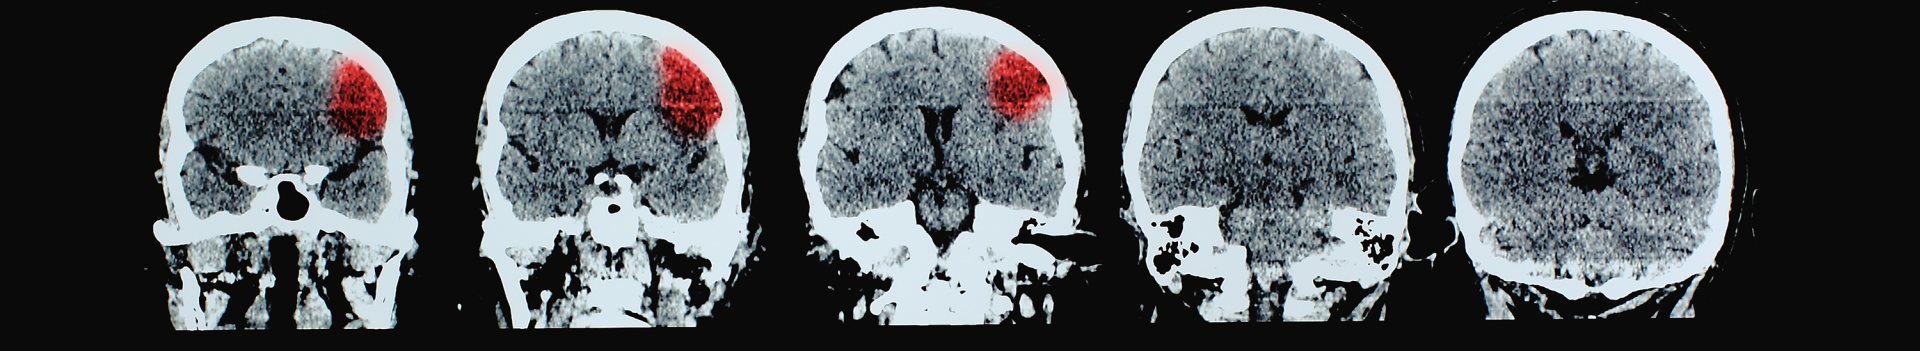

Stroke is the second most common cause of death worldwide and a major cause of disability. Improvements in prevention, acute treatment and rehabilitation have led to a decrease in the incidence and mortality from stroke, however, there is an expected increase in the volumes of stroke due to population growth and ageing.